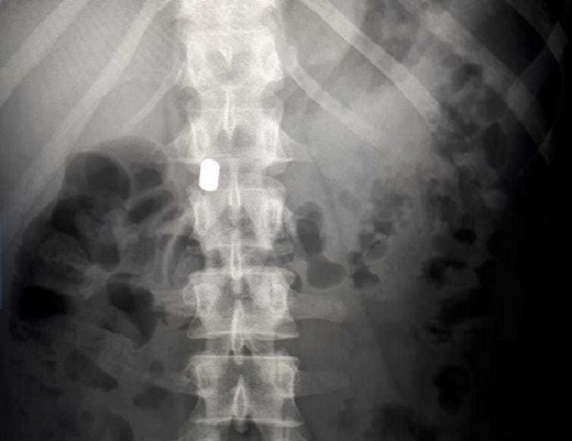

Девочка поступила в больницу 16 мая с жалобами на боли в животе. Врачи провели рентгенографическое исследование и обнаружили в брюшной полости инородные предметы.

«Два магнитных цилиндра находились в желудке, два – в двенадцатиперстной кишке. Они уже начали продавливать стенки, что привело бы к перфорации кишечника. Еще сутки и мог возникнуть перитонит, который обернулся бы тяжелыми последствиями для здоровья ребенка», – рассказал главный врач БСМП № 2 Андрей Караваев.